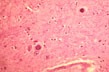

Fig 34 - Lafora bodies in the brain.

Dense intraneuronal

inclusions.  H&E Stain